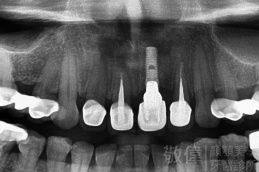

人工植牙/上顎前牙植牙重建

治療前-缺上排前牙   治療後

治療前-全口X光   治療後-全口X光